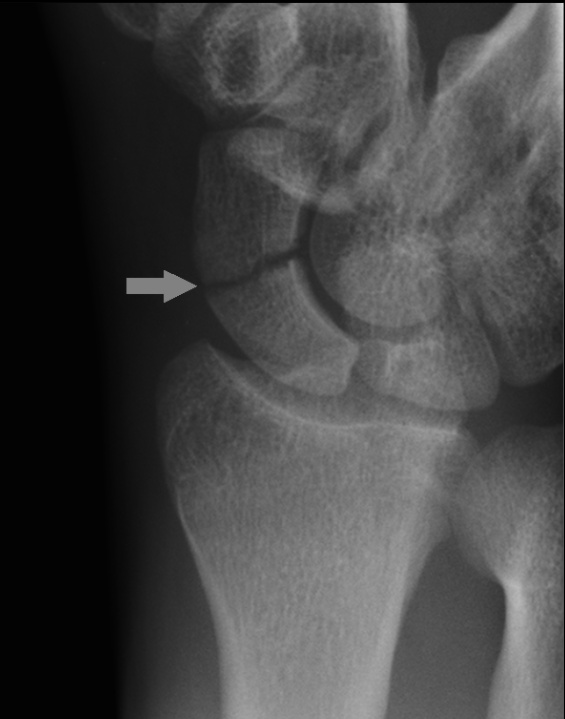

Scaphoid

Scaphoid fractures are the most common fracture amongst all of the carpal bones.

Scaphoid fractures are the result of a fall on an outstretched hand that is radially deviated.

Patients with a scaphoid fracture will present with point tenderness in the anatomical snuff box of the affected hand and local swelling.

Scaphoid fractures are difficult to diagnose because they are not detected on x-ray for up to two weeks after the injury. CT/MRI can be used to confirm diagnosis.

Nondisplaced scaphoid fractures are treated with a thumb spica cast, but displaced fractures require open reduction internal fixation.

Blood flow in the scaphoid is retrograde, from distal to proximal, so waist (the narrow part of the scaphoid) fractures carry a high risk of avascular necrosis if not properly identified and treated.

case: Physical examination shows mild swelling at the dorsum of the right wrist. There is maximal tenderness proximal to the base of the first metacarpal, and the pain worsens with radial deviation of the wrist. Radiographs of the wrist in multiple views reveal no fracture or dislocation. Which of the following is the most appropriate next step in management of this patient?